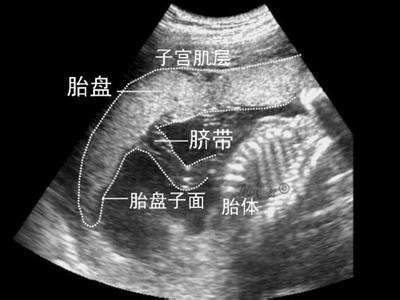

第三,从生理上,众所周知,母体和胎儿之间有个叫“胎盘”的屏障,药物想从母体血液进入胎儿体内,可要通过胎盘这个屏障,药物需要弱酸或弱碱性的,要脂溶性的,要分子量小于600以下的,即使通过了胎盘,遇到月份大的胎儿,胎儿肝脏的“首过效应”也会代谢掉很多药物。